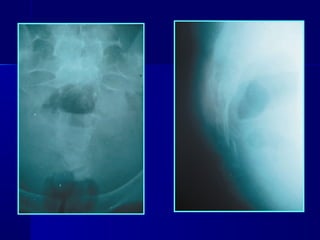

RADIOGRAPHIC INVESTIGATION

• AP radiographs, inlet and outlet views

• Difficult – complex shape (50% are missed)

• Findings – low lumbar transverse process fractures

- asymmetrical sacral foramen

- irregular trabeculation of the lateral

masses

• Sacral arcuate lines ® asymmetry: uncomplicated

sacral frx

® disorganized: comminuted